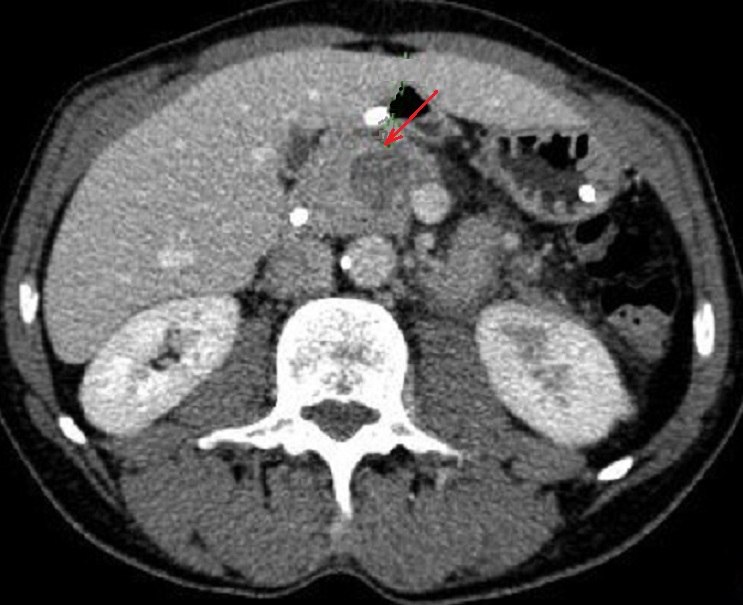

En cas tumeur cephalique ,

image radiologique de dilatation en amont du canal

pancreatique principale et des caneaux secondaires

parfois en se voyaient . Image radiologique TDM d'une

adenocarcinoma de la tete du pancreas avec effet de

dilatation legere en amont du CPP |

Une autre cas de tumeur

cephalique avec image de dilatation du canal

principale et atrophie parenchymateuse en amont du

pancreas . Image radiologique TDM en coupe axiale |

|